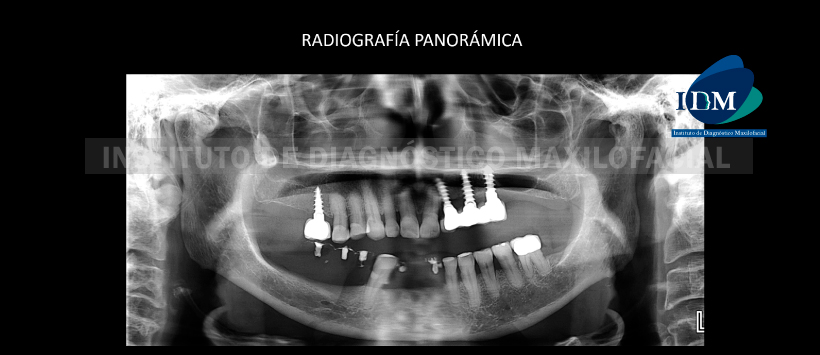

Paciente de 81 años de sexo femenino acude al Instituto de Diagnóstico Maxilofacial para planificación de implantes.

En la radiografía panorámica se aprecia una alteración de la morfología y estructura de ambos cóndilos mandibulares compatible con proceso degenerativo (probable osteoartrosis), neumatización de ambos senos maxilares, reabsorción ósea alveolar severa bimaxilar, edéntulo parcial bimaxilar, múltiples implantes, coronas protésicas y múltiples restauraciones. Sin embargo lo mas resaltante es la pieza 18, la cual se encuentra en posición vertical y proyectada sobre el seno maxilar derecho. (Figura 1)